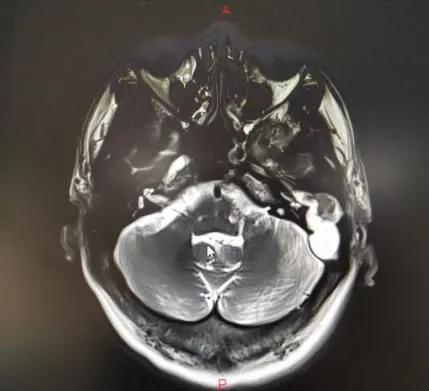

当地医院骨科将武先生诊断为颈椎病,后来又辗转几家医院仍无法确定病因……后来武先生住进郑州市中心医院神经外科,头颅MRI显示:左侧颞叶脑脓肿、中耳乳突炎。原来是因剧烈头痛再发“颅内感染”。

既没有基础疾病,也没有外伤病史,好端端的怎么会反复颅内感染呢?看着武先生的影像片子,神经外科医师突然想到:会不会是中耳炎侵袭到颅内导致的颅内脓肿和感染呢?!随即,该医师迅速联系耳鼻咽喉头颈外科主任李玉杰,详细询问病史、查体和全面查看影像学片子。

李玉杰主任认为,这是一例巨大“中耳胆脂瘤”破坏周围骨质后,蔓延至颅内引发的严重颅内外并发症。病根在中耳,必须尽快手术!

病因找到了,然而手术却是个难题!术前患者因中耳胆脂瘤导致的周围骨质破坏先后引起乙状窦血栓性静脉炎、硬脑膜缺损、脑膜炎、脑脓肿、迷路炎、面肌痉挛等多种颅内、外并发症,手术过程存在着巨大的风险,手术难度大,风险极高!